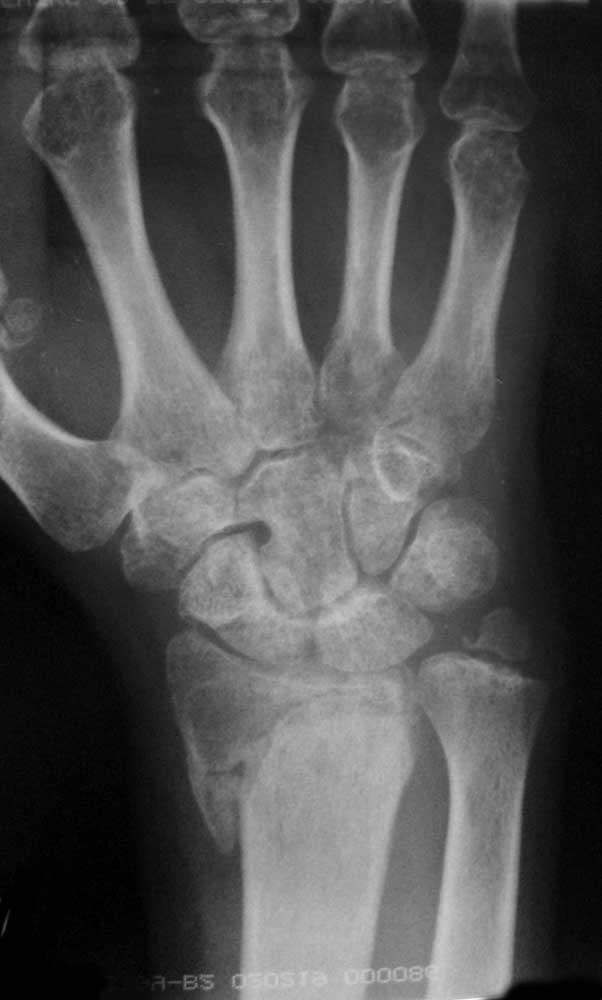

правая кисть - прямая проекция и разные степени проекции

http://s05.radikal.ru/i178/0911/16/9cc733bcfbf2.jpg

прямая проекция и с согнутыми в кулак пальцами

Здравствуйте! Предлагаю произвести открытую репозицию отломков ладонным доступом, остеосинтез пластиной с угловой стабильностью или несколькими спицами. Рентгенографически имеются признаки пятнистого остеопрозоа костей кисти (синдром Зудека) -- следовательно во время открытой репозиции произвести декомпрессию тунельного канала.

Николай, поясните, пожалуйста, как декомпрессия карпального канала при предполлагаемом синдроме Зудека(Reflex Sympathetic Dystrophy)должна должна помочь пациенту? Признаков синдрома карпального канала у пациента нет. Достаточно ли данных для диагностики синдрома Зудека? Остеопороз может быть вызван иммобилизацией, для боли и уменьшения объема движений тоже есть причины.